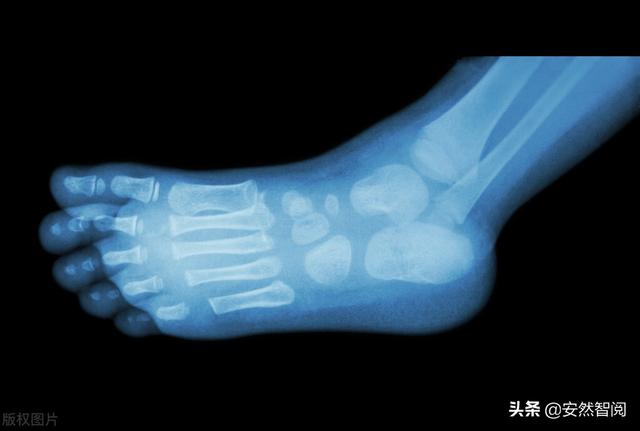

脚部疼痛患者做的X光片